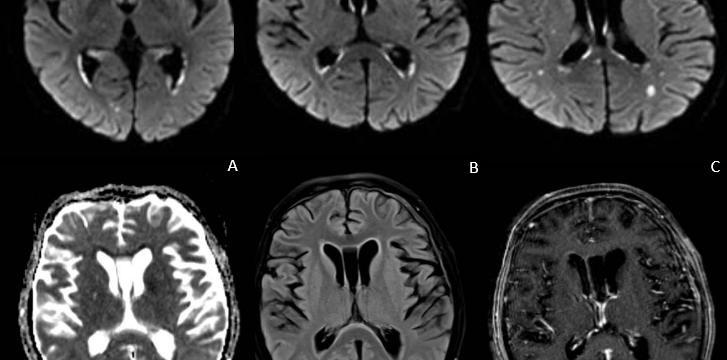

Mujer de 69 años de edad, con un cuadro de 7 meses de inestabilidad cefálica y de la marcha. Se realiza una RM craneal inicial, que es normal. Progresivamente, la síntomatología empeora, añadiéndose desorientación, alucinaciones, mioclonías y deterioro cognitivo. Se repite RM craneal por empeoramiento clínico progresivo.